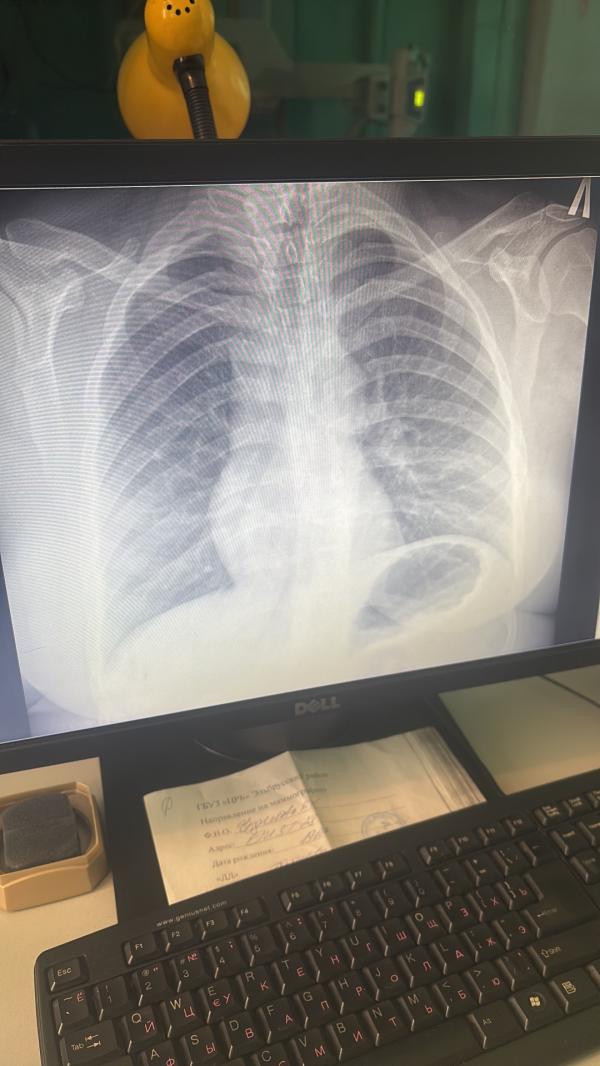

Девочки тут бронхит или пневмония